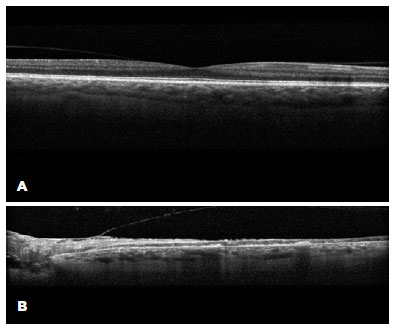

At 1-month follow-up, the patient was comfortable without eye pain. The examination revealed a VA of 20/20 in the right eye and NLP in the left eye, normal IOP, trace left lower lid ectropion and trace chemosis in the left eye, and notable pallor of left optic nerve, a fibrotic membrane extending across the macula, and sclerotic vessels. OCT revealed atrophy and destruction of both inner and outer layers of the retina in the left eye, consistent with sequelae of profound retinal ischemia (Figure 4). Fluorescein angiography was not performed. The patient was advised on monocular precautions and routine ophthalmic follow-up.

02-fig04.jpg)

While the most frequently described etiology of vison loss in CST and resultant orbital compartment syndrome (OCS) is optic neuropathy(7,8), a few cases with retinal ischemia and atrophy secondary to vascular occlusion have been reported(9-11). This is the first case to demonstrate OCT findings of retinal ischemia and atrophy secondary to CST and OCS, confirming the notion that retinal arterial occlusion can in fact occur in OCS and CST and lead to visual decline, particularly in the setting of severely elevated IOP. Furthermore, OCT revealed a profound destruction of all retinal layers in the left eye in this case, implicating the involvement of either 1) both the central retinal artery (CRA) that supplies the inner retinal layers and short posterior ciliary arteries (SPCA) that supply the outer retinal layers or 2) the ophthalmic artery that supplies the two aforementioned arteries(12). While occlusion of the intracavernous segment of the internal carotid artery (ICA) and/or CRA is known to cause visual impairment in CST(13), occlusion of either the SPCA or ophthalmic artery without intracavernous ICA occlusion, as in the present case, has never been described, highlighting a unique pathophysiology of vision loss in CST.